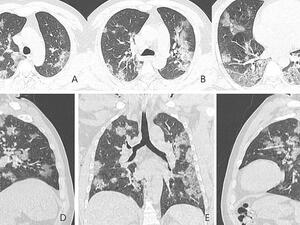

Shocking X-ray images show what coronavirus does to victims' lungs (Twitter)

March 12th, 2020 - 08:30 GMT

X-ray Images Show How Coronavirus Ravages The Lungs!